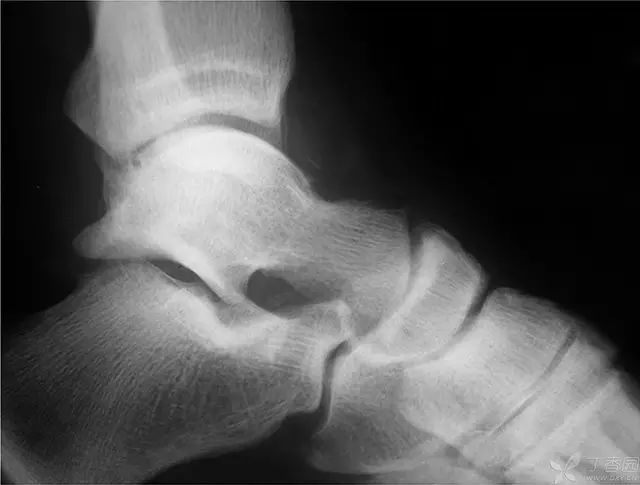

术后 2 周 MRI,没有急性炎症反应

6 个月,有轻度信号改变,表明存在一定程度的生理活动,无骨坏死征象

术后 2 年 MRI,弥漫性信号改变,符合早期骨坏死,但无塌陷

5 年 MRI,弥漫性信号局限在距骨体中心部位,头颈部逐渐出现血运重建,无塌陷